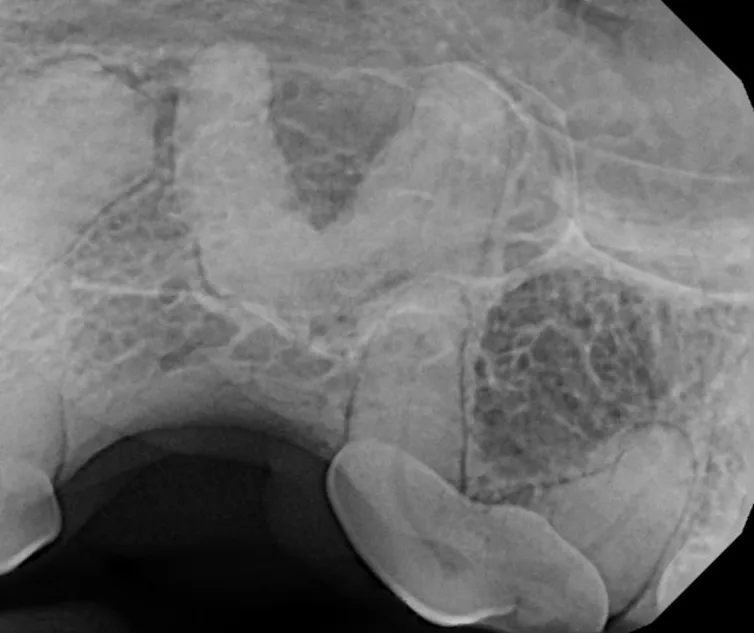

Cone Beam Computed Tomography

The Center now provides advanced imaging via cone beam CT. Cone beam CT is excellent for visualization of bony structures of the skull, nasal cavity, teeth, and ears. Cone beam CT is especially helpful for diagnosing dental disease and evaluation of jaw fractures. It can also be useful for evaluating the sinuses and tympanic bulla. Cone beam CT can be used in conjunction with nasal biopsy and culture to evaluate nasal discharge whether chronic or acute.